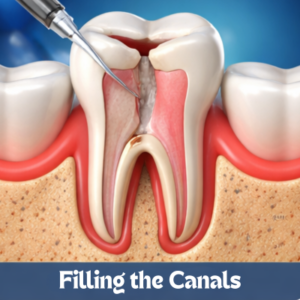

ROOT CANAL

ROOT CANAL

ROOT CANAL

ROOT CANAL